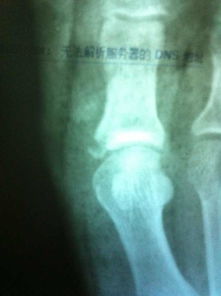

拆除石膏后,許多病人感到關(guān)節(jié)不舒服,有疼痛感。因為關(guān)節(jié)長期固定后,關(guān)節(jié)內(nèi)粘連,軟組織攣縮,所以活動時關(guān)節(jié)不適是正?,F(xiàn)象。此外,拆除石膏后,病人必須照 X 線片,以便明確骨折愈合的情況。若骨折尚未愈合,千萬不要伯麻煩,還需要重新固定。若骨折已愈合,此時必須逐步加強功能鍛煉。同時由于此時骨折愈合尚不牢固,而且長期固定后,骨代謝有所改變,骨質(zhì)明顯疏松,所以應(yīng)當避免某些可能導(dǎo)致再骨折的動作,更應(yīng)避免再次外傷。再次骨折后,骨折愈合更為困難,而且需要再固定,關(guān)節(jié)的功能將會受到無法挽回的影響。當然也應(yīng)當消除不必要的顧慮,有些病人由于害怕再骨折,拆除石膏后,不敢活動關(guān)節(jié),不敢進行鍛煉,這樣反而會影響骨折愈合。影響肢體功能的恢復(fù)。